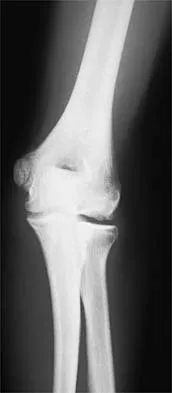

Question 67 High Yield

A 32-year-old laborer reports left ankle pain and deformity. History reveals that he sustained a left ankle fracture 2 years ago and was treated with closed reduction and casting. Radiographs are shown in Figures 25a through 25c. What is the most appropriate management?

Detailed Explanation

Corrective osteotomy of fibular malunions, with appropriate lengthening, even in the presence of early arthritis, has been shown to decrease ankle pain and increase stability. Reduction and bone grafting of the medial malleolar nonunion is also needed. There is no evidence supporting the use of intra-articular steroids or hyaluronic acid in the ankle joint. Lateral talar displacement of even 1 mm has been reproducibly shown to decrease tibiotalar contact by 40% to 42%, causing a predisposition to arthritis. Weber D, Friederich NF, Muller W: Lengthening osteotomy of the fibula for post-traumatic malunion: Indication, technique and results. Int Orthop 1998;22:149-152. Lloyd J, Elsayed S, Hariharan K, et al: Revisiting the concept of talar shift in ankle fractures. Foot Ankle Int 2006;27:793-796. Offierski CM, Graham JD, Hall JH, et al: Later revision of fibular malunion in ankle fractures. Clin Orthop Relat Res 1982;171:145-149.